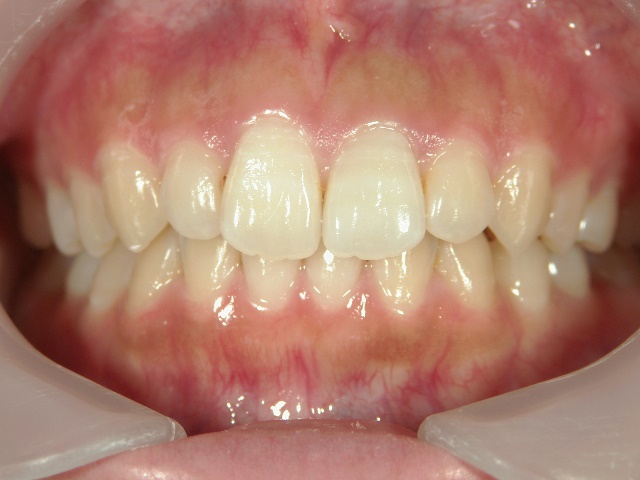

矯正歯科 治療後 正面

矯正歯科 治療後矯正歯科 アクアシステム(透明マウスピース矯正) 治療後矯正歯科(アクアシステム)治療後